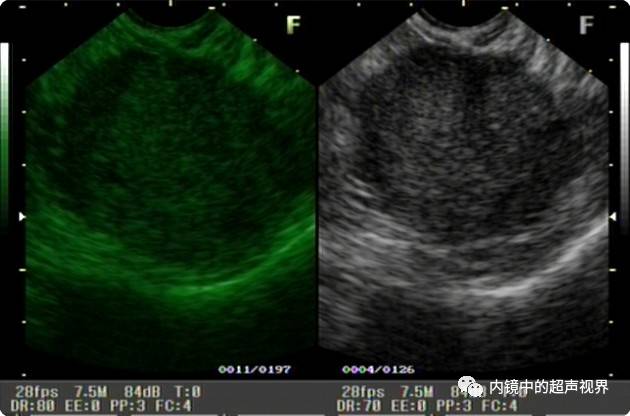

再来一纵隔肿物的图片,是DR30和80的对比,很明显。

纵隔肿物